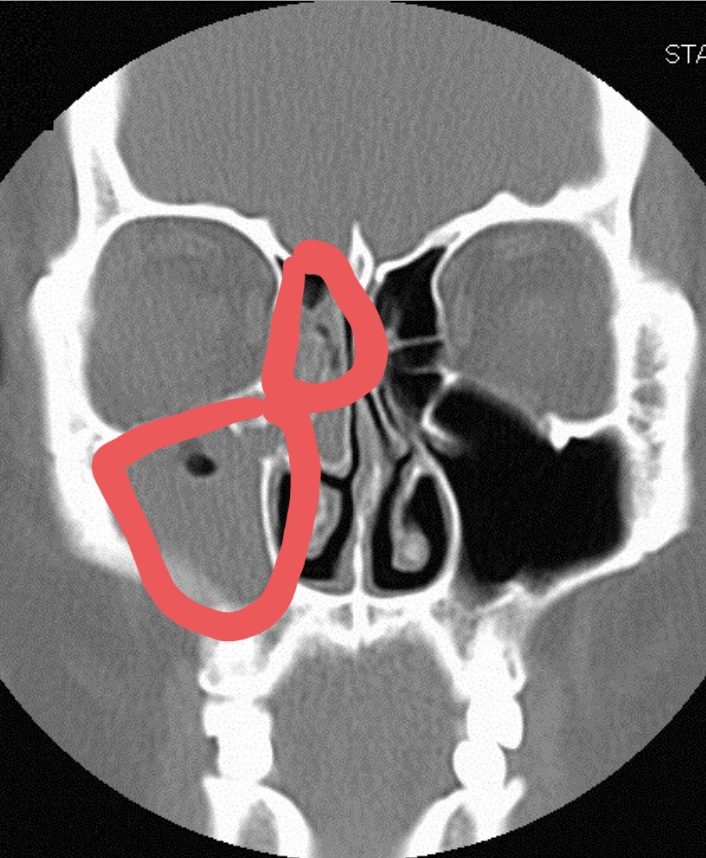

비강과 부비강을 잇는 좁은 문과 같은 입구가 붓고 콧물이 제대로 순환되지 않으면 코와 눈 주위에 그림처럼 빈 공간이 있는데, 비어 있어야 하는 분홍색과 하늘색 부분에 고름이 올라오는 것을 부비강염이라고 합니다.

그래서인지 그 부위를 만질 때 통증도 같이 있었는데 저같은 경우에는 오른쪽 그림의 빨간색으로 체크했듯이 미간과 눈 앞 꼬리에서 눈 밑까지 누르면 상당히 아픈 통증이 있었습니다.광대뼈 아래 뺨의 부부가 누르지 않아도 뻣뻣해지는 느낌이 들었고 #관자놀이의 통증과 치통이 심했어요.

제 엑스레이는 아니지만 가능한 한 비슷한 사진을 보면 위의 사진처럼 붉은 부분이 반대쪽처럼 검게 비어 있어야 하는데 사진처럼 곪아 있더군요.

콧물이 순환하는 입구의 점막이 부어 있고, 양쪽이 딱 붙어 있었습니다. ;;;